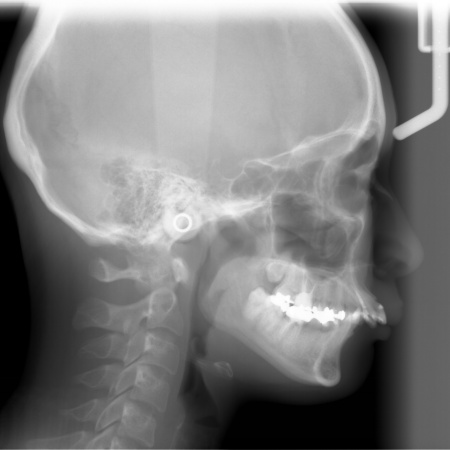

| カウンセリング | 拝見したところ、上前歯が大きく前に出ている上顎前突であり、上下の前歯が噛み合わずに口を閉じても前歯同士が接触しない「開咬(かいこう)」の状態でした。 レントゲン撮影をして詳しく調べた結果、歯の位置だけでなく、骨格的な問題があることが分かりました。 また、前歯で食べ物をうまく噛み切ることができないため、奥歯にも強い負担がかかっているだけでなく、このまま放置すると、奥歯がすり減ったり痛みが生じたりするリスクもあります。 以上のことから、噛み合わせを改善する治療が必要だと診断しました。 |

患者様の場合、骨格的な上顎前突が噛み合わせを乱している主な原因であることから、矯正治療では前歯を後方へ大きく動かすためのスペースを確保する必要があります。 そのため、今回は以下2つの方法を提案しました。 ①抜歯後、アンカースクリューを用いたワイヤー矯正 メリット:骨格的な上顎前突に対応しやすく、前歯を大きく後方へ動かすことができる ②取り外し可能な装置を使用するマウスピース矯正 メリット:装置が透明で目立ちにくく、取り外しができる 以上のメリットとデメリットを丁寧にお伝えしたところ、患者様は①のアンカースクリューを用いたワイヤー矯正を選択されました。 まず、上顎の左右奥歯を抜き、前歯を後方に動かすためのスペースを確保します。 治療の結果、前歯が正しく噛み合うようになり、横顔のバランスも整いました。 矯正治療終了後は、歯が元の場所に戻らないよう上下前歯に保定装置(リテーナー)を装着し、治療を終了しています。 |